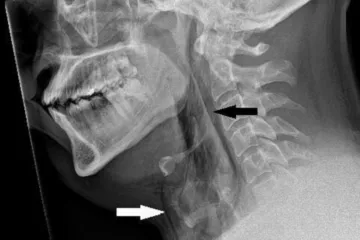

Kýchnutí se nesnažte potlačit, varují lékaři po případu protržené průdušnice

Když cítíte, že se blíží kýchnutí, je lepší se ho nesnažit potlačit, upozornili skotští lékaři. Vychází při tom z případu popsaného v odborném časopise BMJ Case Reports, kdy si muž při pokusu potlačit kýchnutí při řízení spontánně protrhl průdušnici, napsal list The Guardian.